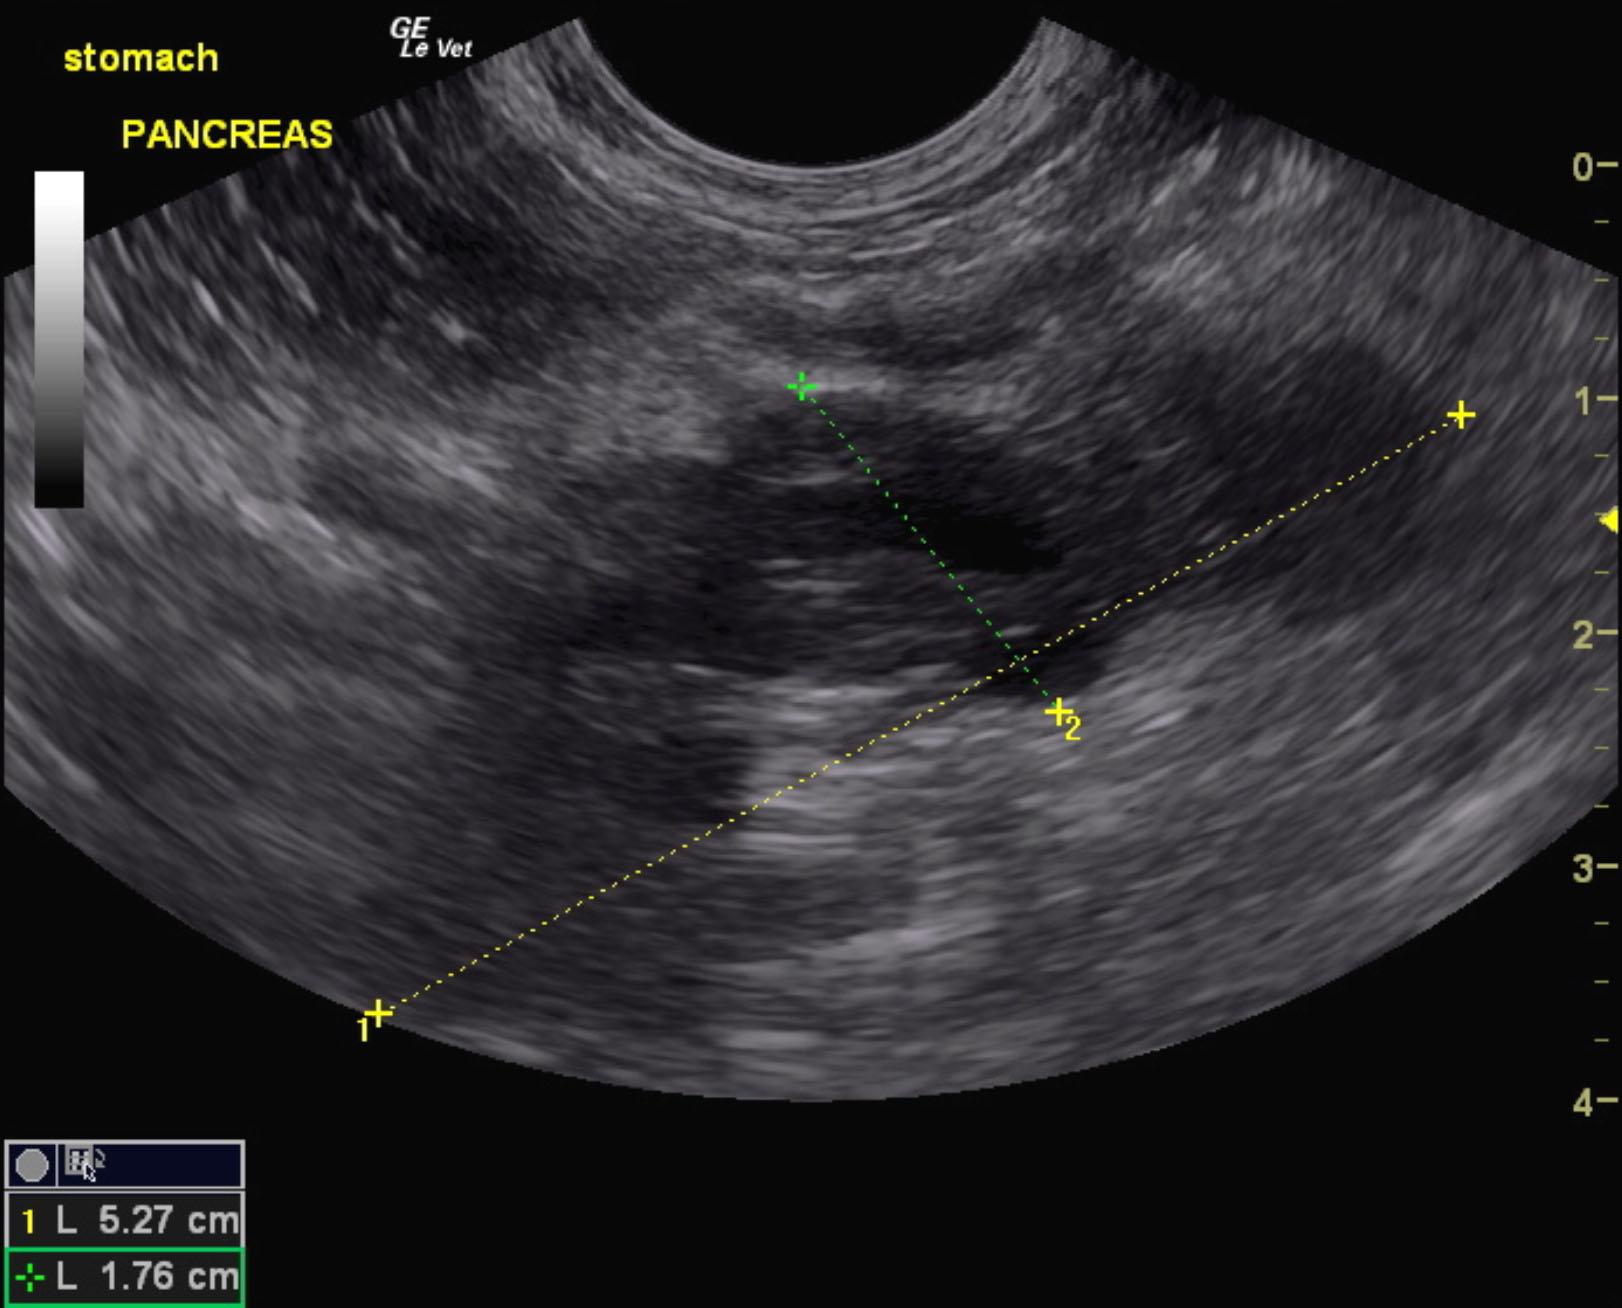

A 10-year-old female spayed DSH cat was presented for evaluation of intermittent diarrhea, weight loss, and anorexia. Blood work was unremarkable.

A 10-year-old female spayed DSH cat was presented for evaluation of intermittent diarrhea, weight loss, and anorexia. Blood work was unremarkable.